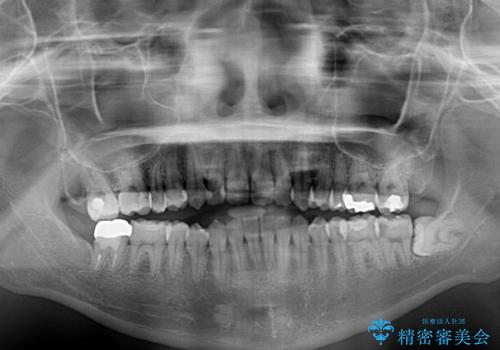

- オープンバイトのため、話しているときの見た目が気になるとのことで来院された患者様です。

下顎骨は左側にシフトしており、咬み合ったときには奥歯と前歯の一部しか接触していない状態でした。

骨格的な左右差は歯列矯正は改善できないため、上下歯列が全体的に接触することをゴールとしてインビザラインにて矯正治療を行うこととしました。

前歯のデコボコの解消と並行して上下の奥歯を圧下させるようにすることで、前歯を接触させるように計画しました。

上下の隙間に舌が入り込むことがオープンバイトの原因であったため、舌の筋肉のトレーニングも並行して行い、後戻りの抑制を図りました。